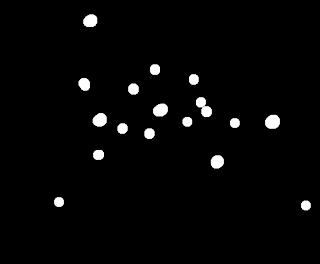

With this, we may now look for cancer cells! Using the fact that the average area of a normal cell is ~ 444 pixels, we can make a circle with the same size and use this as strel to process the image of normal with cancer cells. First we binarize the image,

|

| Binarized image of normal cells with abnormally large cancer cells. |

Then, use the opening operation with the circular strel,

|

| Applying the opening operation on the binarized image. |

Do you see the cancer cells now? There are only 5 of them, but still too many normal cells here. Let's see if applying the opening operator again can remove these.

|

| The opening operation applied twice. |

Now there's the five cancer cells with two outliers. Not bad. :D